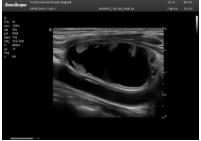

1單晶體凸陣探頭

采用了單晶體探頭材料,探頭面是凸面,接觸面小,成像視野呈扇形,應(yīng)用廣泛,常應(yīng)用于腹部、婦產(chǎn)、肺部等相對(duì)部位較深的臟器。

超聲圖像是探頭和系統(tǒng)平臺(tái)緊密結(jié)合的產(chǎn)物,因此在同一臺(tái)機(jī)器上,軟件、硬件都需要達(dá)到單晶探頭的要求。

肝癌